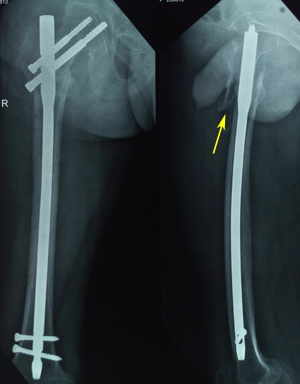

We have 4 cases of varus mal-reduction. Out of these 4 cases, two patients developed cutout, rest of the two went into successful varus mal-union. The 2 cutouts in our study had a fracture classification of 31-A2.3 and 31-A2.2. In addition, the fractures were inadequately reduced and noted to be fixed into a varus position (Figure 5a & b). Placement of hip screw is critical in the ultimate successful outcome of unstable trochanteric fractures. The tip-apex distance (TAD) has been described by Baumgaertner and associates22,23 as a useful intraoperative indicator of deep and central placement of the lag screw in the femoral head, regardless of whether a nail or a plate is chosen to fix the fracture.19 Position of hip screws in head and neck is dependent on quality of reduction. Varus reduction causes placement of hip screws in superior part of head and neck, leading to varus collapse and early cutout (Figure 5b & c). It is important to note that absolute anatomical reduction of unstable trochanteric fractures is a wishful thinking. One should target to achieve antero-medial reduction with correct neck shaft angle. P Janardhana Aithala15 also reported that maintenance of correct neck shaft angle and version leads to union, irrespective of comminution and non-anatomical reduction. Hence, the most important technical aspect of PFN implantation is maintaining the appropriate neck shaft angle so as to place hip screws in desirable position. Both are interlinked as screw placement angle is prefixed and hence unless good neck shaft angle is achieved, it is impossible to put the hip screw correctly. In the AP projection, varus at the fracture site is the main hitch to place the screw in centre or inferiorly, while in lateral projection posterior sagging or flexion of proximal fragment is the problem in putting the hip screw centrally. Several studies have reported a cutout rate of 2%–8%.10,26-31 We observed a cut-out complication in two patients (4.76%). One of them underwent partial hip arthroplasty, whereas the other one opted for implant removal only. Considering the two cut-outs in our study with resultant fixation failure, we believe it is more of technical failure rather than failure of implant. Proper execution of the procedure will give superior results. Our recommendation for lag screw placement position especially in dual screw nails is inferior in AP projection and central in lateral projection.

Figure 5b Post-operative radiograph showing varus mal-reduction (pointed by thin arrow as medial overlap of fragments). Also note the superior position of the screws (thick arrow).

Figure 5c Six weeks post-operative radiograph showing varus collapse (thin arrow), cut-out (thick arrow) and fixation failure.

Though, postoperative non-union of intertrochanteric fracture is relatively rare, we had 2 cases of cutout leading to non-union. Factors contributing for non-union were fracture fixation in varus, superior placement of screws, osteopenia, and unstable fracture geometry. In our cases, even after fixation of a fracture with PFN, local instability at fracture site persisted leading to abnormal stresses and the fixation failed to provide a stable mechanical environment for fracture healing. One patient underwent arthroplasty procedure while other opted for implant removal only. Radiographic images of one patient are presented in Figure 5.